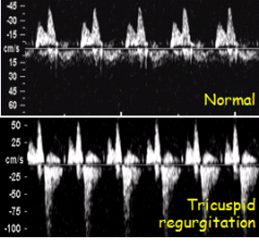

Flujo tricuspídeo

- Patrón normal cuando no hay regurgitación en sístole

- Regurgitación durante la mitad de la sístole al menos y con una velocidad de más de 60 cm/s